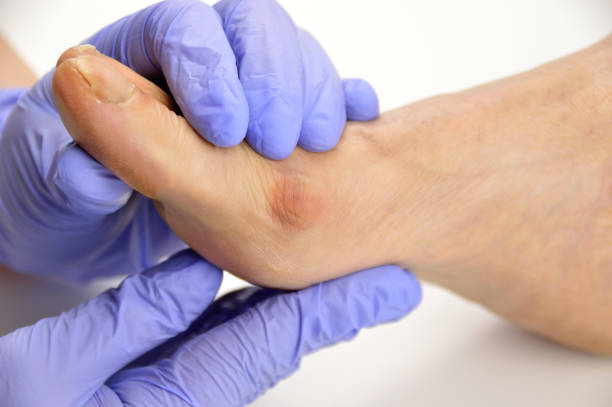

발 마사지를 통해 발 아치 주변의 근육을 이완시키고 혈액 순환을 촉진하세요. 특히 엄지 발가락 주변을 집중적으로 마사지하면 무지 외반증 관리에 도움이 됩니다.

무지 외반증의 심각한 경우에는 전문가 상담을 고려해야 합니다. 물리치료사나 발건강 전문가와 상담하여 적절한 치료 방법을 찾아보세요.